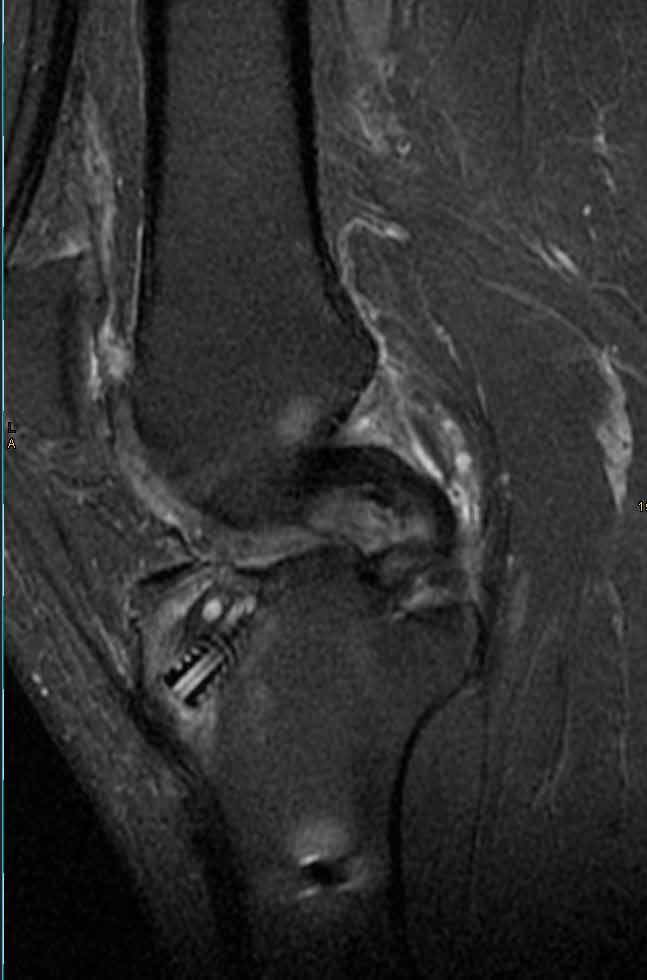

Weißes Gold im Knie

Die Prothese, das ist der Heavy Metal der Orthopädie – und meist der Standard, um Patientinnen und Patienten mit fortgeschrittener Arthrose in den großen Gelenken zu behandeln. „Oft ist es auch die richtige Therapiewahl“, sagen Christian Benker und Dr. Mark Schmolze vom Endoprothetikzentrum an der Klinik Hohe Warte. Sie sagen aber auch: Ansetzen sollte man viel früher. Am Knorpelkompetenzzentrum der Klinikum Bayreuth GmbH an der Klinik Hohe Warte setzt man auf das weißes Gold: den Knorpel. „Es gibt sehr gute Möglichkeiten, einen defekten Knorpel wieder aufzubauen“, sagt Benker. „Und das kann Patientinnen und Patienten oft über einen langen Zeitraum die Prothesenversorgung aufschieben oder sogar ersparen.“

Teil- und Vollprothesen, Individualprothesen, Wechseleingriffe – als Hauptoperateure des Endoprothetikzentrums haben Benker und Schmolze das gesamte Spektrum des Gelenkersatzes zu bieten. Die richtige Therapie beginnt in ihren Augen aber bereits lange vor dem Gelenkersatz. Die beiden Ärzte sind nicht nur Hauptoperateure im Endoprothetikzentrum, sie sind zudem Mitglieder im Qualitätskreis Knorpel-Repair & Gelenkerhalt e. V. und haben an der Klinik Hohe Warte ein Knorpelkompetenzzentrum etabliert.

Ein guter Nachbau

Im Knorpelkompetenzzentrum machen sich Benker und Schmolze zunächst beim Röntgen und wenn nötig beim MRT ein Bild: Wie weit ist der Knorpelschaden fortgeschritten? „Wir können die Arthrose noch nicht heilen, aber mithilfe von zum Beispiel zellfreien Implantaten die lokal begrenzten Defekte reparieren. Beim sog. „MincedCartilage“ wird eine kleine Menge körpereigenes Knorpelgewebe entnommen und zerkleinert. Mit dieser Masse wird der Defekt aufgefüllt und durch ein Kollagen-Implantat verschlossen. Innerhalb von Wochen bildet sich neuartiges Knorpelgewebe.

Bereits vor mehr als zehn Jahren hat man an der Klinik Hohe Warte begonnen, Knorpelgewebe zu transplantieren. Autologe Knorpelzelltransplantation (ACT) nennt sich dieses Verfahren. Vereinfacht gesagt, wird dem Patienten dabei arthroskopisch Knorpelgewebe entnommen, das dann im spezialisierten Labor über einige Wochen „gezüchtet“ wird. Nach etwa vier Wochen wird der Knorpeldefekt dann operativ durch den eigenen, nachgezüchteten Knorpel ersetzt.

Und die beste Nachricht: „Beide Behandlungen bieten eine weitere Chance. In nur einem Eingriff können wir auch eine bestehende Fehlstellung der Beinachse – und damit eine mögliche Ursache für die Arthrose – korrigieren“, sagt Benker. Diese Therapien können einen künstlichen Gelenkersatz nicht nur hinauszögern, sondern im besten Fall sogar verhindern, so Benker und Schmolze. „Wir möchten, dass unsere Patientinnen und Patienten über einen möglichst langen Zeitraum schmerz- und beschwerdefrei leben. Die richtige Alternative finden wir als Team mit unseren Patienten gemeinsam.“

Technik, die tief blicken lässt: Neuer Arthroskopieturm für die Orthopädie